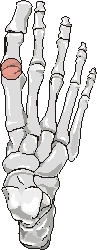

Gout: Erosions 1st MTP joint with preservation of joint space

+ ++